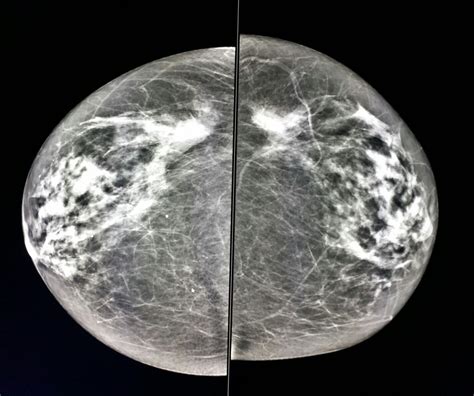

Normal Mammogram Images

Breast cancer is a significant health concern for women worldwide, and early detection through mammography plays a crucial role in improving outcomes. Mammography involves using low-energy X-rays to examine the breast tissue and detect any abnormalities. One of the key aspects of mammography is the interpretation of normal mammogram images. Understanding what constitutes a normal mammogram is essential for both healthcare providers and patients.

Normal mammogram images are those that do not show any signs of breast cancer or other abnormalities. These images typically display breast tissue that appears dense or fatty, with no masses, calcifications, or architectural distortions. Understanding the characteristics of normal mammogram images is crucial for radiologists to accurately interpret the results and distinguish them from abnormal findings.

Normal mammogram images can vary depending on the individual's breast tissue density. Breast tissue density is categorized into four types:

Category Description

Almost entirely fatty The breasts are mostly composed of fatty tissue, making it easier to detect abnormalities.

Scattered areas of fibroglandular density The breasts have some dense tissue and some fatty tissue, which can make detection slightly more challenging.

Heterogeneously dense The breasts have a significant amount of dense tissue, which can obscure small abnormalities.

Extremely dense The breasts are almost entirely composed of dense tissue, making it the most difficult to detect abnormalities.

Interpreting normal mammogram images involves a systematic approach to ensure that no abnormalities are missed. Radiologists look for specific features that indicate normality:

• Uniform Density: The breast tissue should appear uniform in density, with no areas of increased or decreased density.

• No Masses: There should be no visible masses or lumps in the breast tissue.

• No Calcifications: There should be no calcifications, which are small deposits of calcium that can sometimes indicate the presence of cancer.

• No Architectural Distortions: The breast tissue should have a normal architecture, with no distortions or pulling of the tissue.